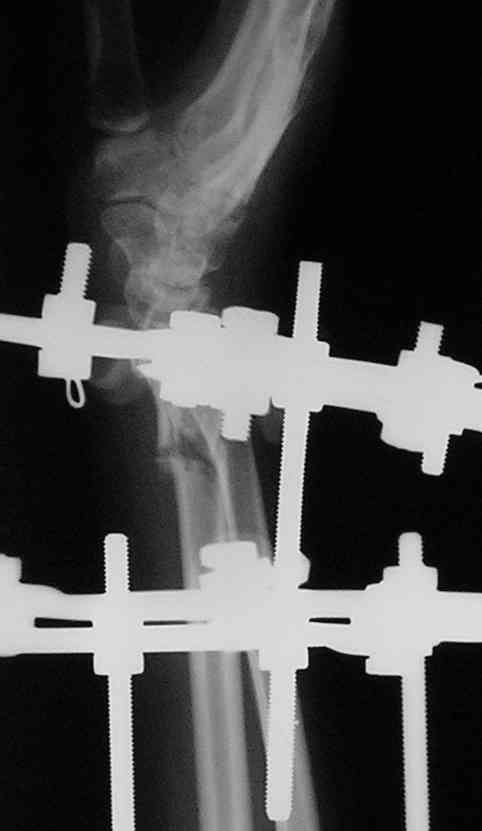

Спице-стержневой аппарат с компактотомией лучевой кости, костная пластика локтевой с удалением пластины. Не комфортно, но больше шансов на благоприятный исход. Заканчиваю лечение с похожей деформацией лучевой кости.

Виктор.

Как насчет наложения шарнирно-дистракционного аппарата на кисть-предплечье с последующими принудительными движениями?

Плюс - если лечить аппаратом, может быть, есть смысл попытаться сделать "закрытую артропластику" шарнирным аппаратом? Подрастянуть сустав, центрировать шарниры по полулунной кости, и принудительно поразгибать аппаратом?